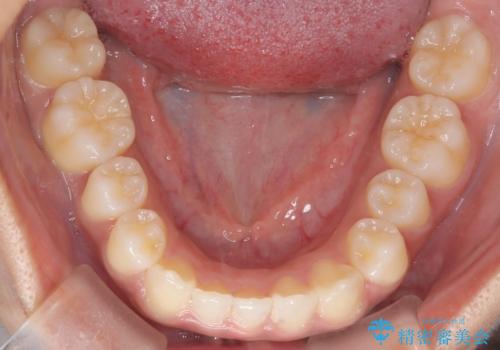

下の前歯が一本足りない患者様でしたので、シミュレーションを作り、事前に患者様と治療ゴールのイメージをしっかり共有したうえでインビザラインを用いて治療を行っています。

下顎の前歯が一本ない場合は上下の正中は合いません。